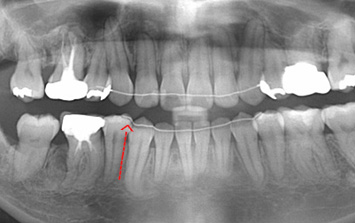

26세 여환으로 우측 아래 어금니 매복으로 다른 치과에서는 어금니 2개를 모두 발치 해야 한다는 진단을 받고 내원.

환자분이 매복된 치아를 꼭 살리고 싶다고 하여 사랑니는 발치를 하고 매복되어 있는 치아는 교정으로 견인 하기로 함.

구강외과 협진으로 안정적으로 사랑니를 발치하고 치아교정을 진행하였습니다.

어금니와 사랑니가 수평 매복되어 있는 상황

사랑니 발치 후 매복된 치아 견인

교정 후 치조골 또한 온전하게 재생됨

구강외과 협진- 사랑니를 발치 한 이유는 매복치아를 발치 할 경우 다량의 뼈를 제거해야 하고

그로 인하여 아래턱뼈가 약해질 가능성이 있다고 판단했기 때문입니다.